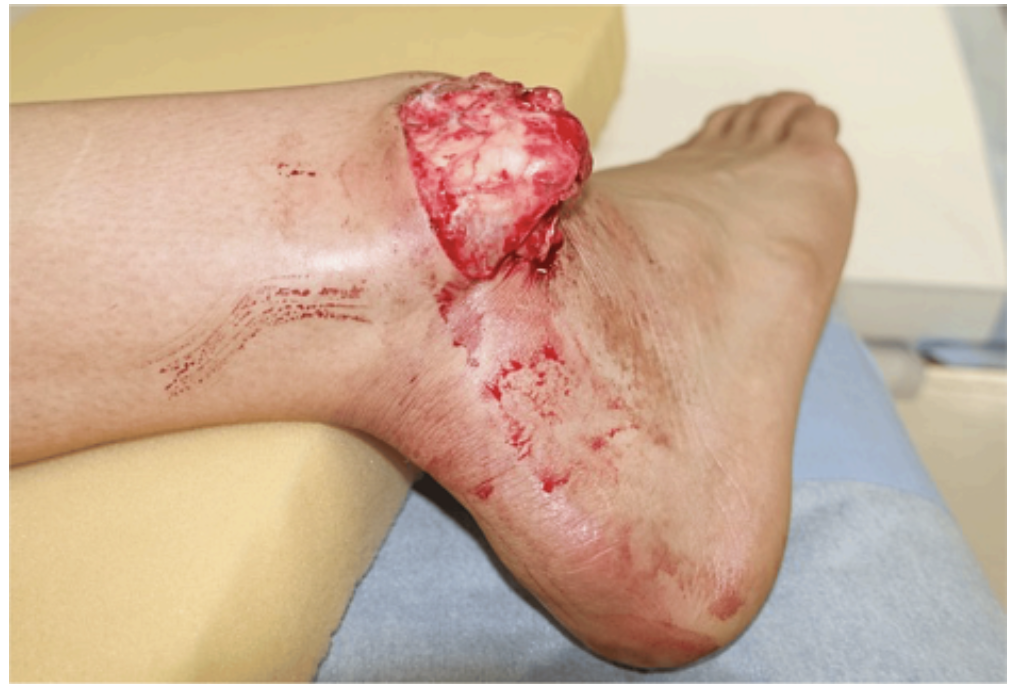

Upon arrival, the patient is in acute distress, screaming in pain, and he is alert and responsive. On physical exam, the patient has an exposed distal fibula and tibia that has punctured through the skin. A tourniquet has been applied proximal to the wound. No active hemorrhage. Pulses are not intact. Sensation is intact in the dorsal aspect of the foot, but decreased in the medial aspect of the foot. Pain medication was given, and labs were drawn.